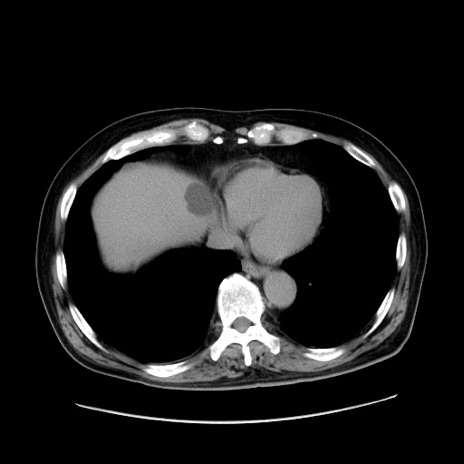

症例30(横断像)

【症例】80歳代男性

【主訴】臍周囲痛

【現病歴】約6時間前から臍下部痛が出現。次第に腹部膨隆・背部痛も生じてきたため来院。背部痛の場所は変化しない。

【身体所見】意識清明、BT 36.3℃、BP  131/87mmHg、P 87bpm、SpO2 100%(RA)、臍周囲自発痛・圧痛あり、反跳痛なし、自発痛部位に一致して板状硬あり、腹部膨隆、腸雑音減弱、CVA tenderness両側陰性。